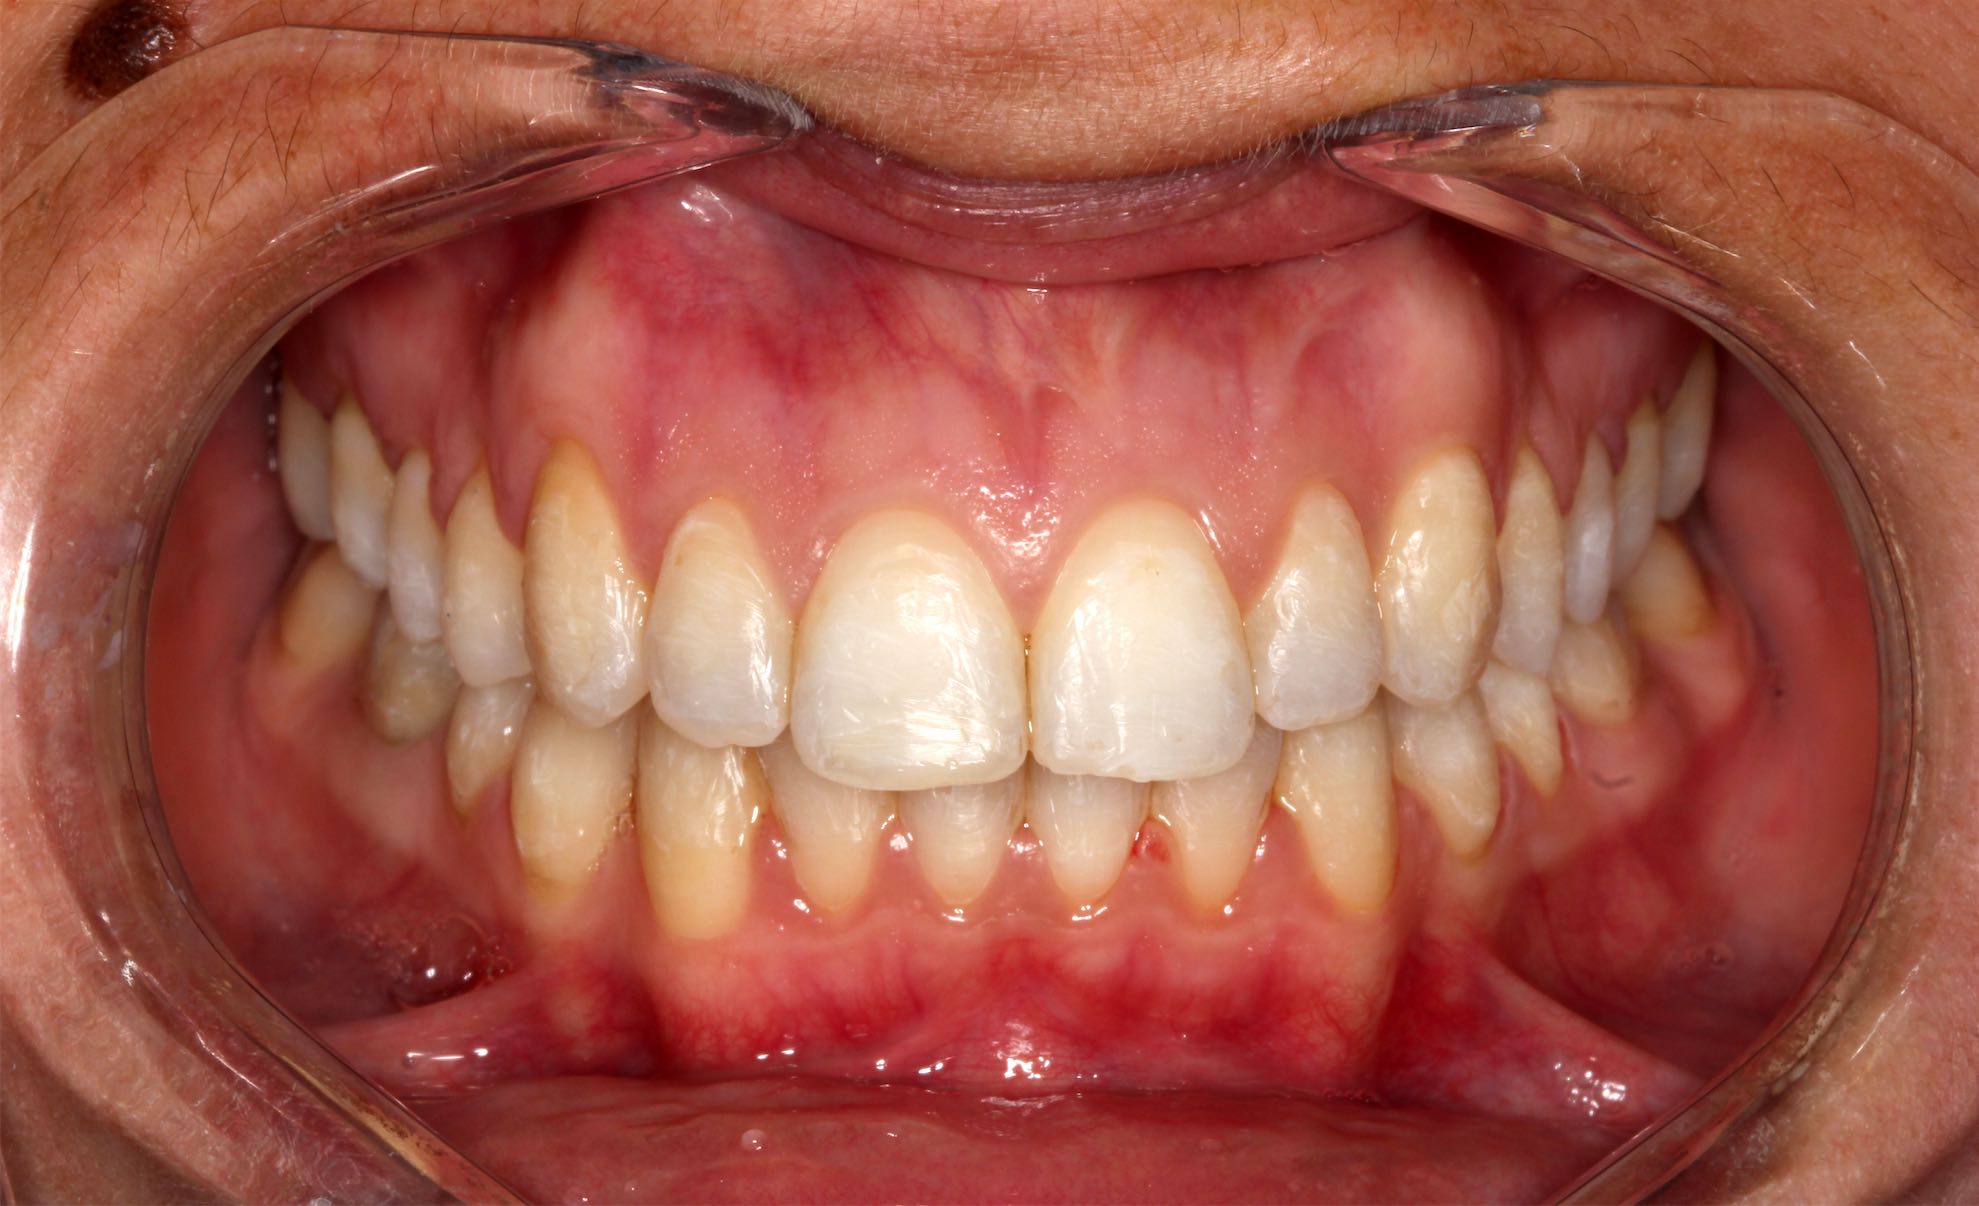

Blanqueamiento Dental

BeforeAfter